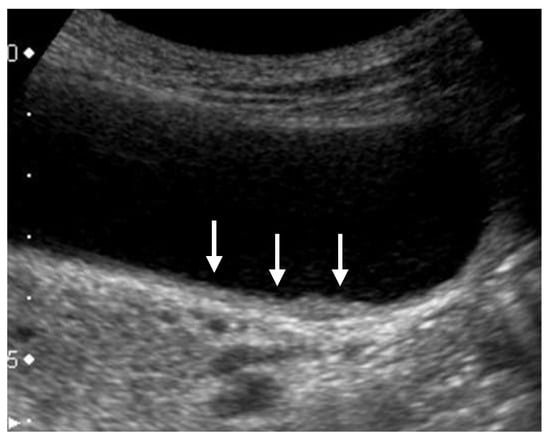

Figure 4. Focal presence of an inner hypoechoic layer (focal GWT). A high-frequency transducer with magnified image showed a slightly thickened inner hypoechoic layer less than 4-mm thick (arrow) in the fundus of GB (GBC case).

GWTs should be determined as wall thickening of 4 mm or more, and subdivided into diffuse and focal [1]. The presence of a partial inner hypoechoic layer of less than 4 mm in thickness (Figure 4) should also be included in focal GWT [1], as it may correspond to early-stage wall-thickening GBC. Diffuse GWT is not a specific US finding for GB abnormalities such as cholecystitis and GBCs; it can also occur in systemic diseases or inflammation of organs adjacent to the GB. However, focal GWT is a specific finding for the GB and is associated with a high frequency of malignant lesions. As GWTs, especially focal lesions, are more difficult to pick up than GPLs, magnification with a high-frequency transducer is strongly recommended (Figure 2). In addition, US evaluation should be performed after appropriate fasting time to rule out the effect of the postprandial contraction.